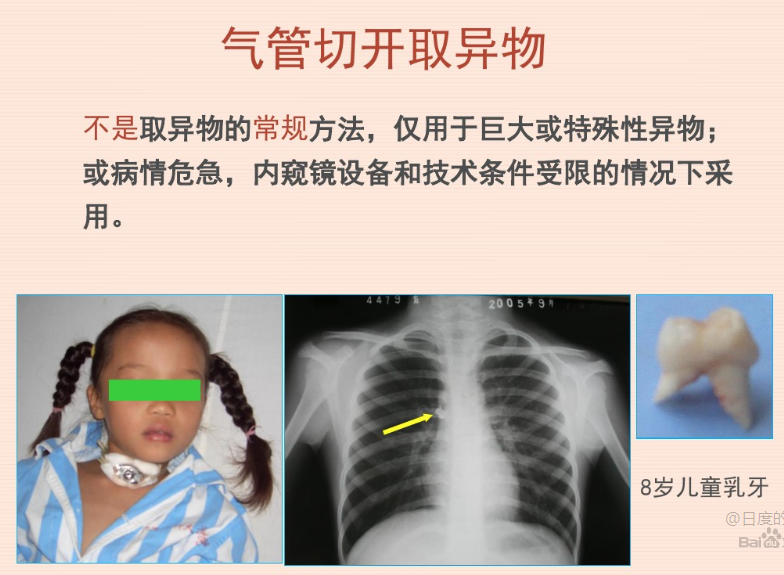

主要指外源性物体经口或鼻误吸入声门,停留于气管、支气管内而致病者。

多发生于5岁以下儿童及脑血管意外后会厌、声门关闭不全的老年人等,偶见于成人。